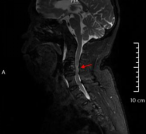

术前影像资料显示C3/C4椎间盘突出、极重度颈椎椎管狭窄、C5/6椎体融合

患者李某,70岁,因“四肢乏力、行走不稳1年,加重1个月”入住新利备用网骨科二区,入院检查诊断为:脊髓型颈椎病、颈椎椎管狭窄症(C3/C4极重度)、慢性不完全性四肢瘫。其中C3/4节段椎管占位率超过50%以上,脊髓受压极其严重,若病情继续进展,可能导致高位截瘫甚至呼吸衰竭,危及生命。且李某还存在C5、6节段先天性融合,短颈畸形,进一步增加了术中暴露和置钉的难度,对主刀医生的经验、技术及团队配合要求极高。